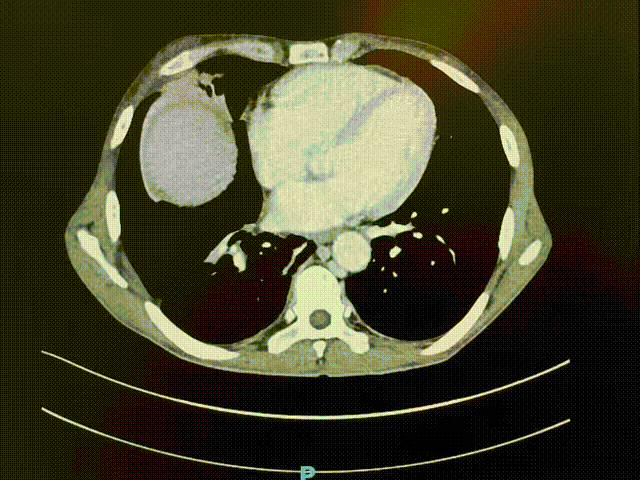

术前增强CT

一次偶然的机会,张阿姨一家了解到西京医院肝胆外科在腹部疑难复杂肿瘤救治领域经验丰富,一家人怀揣孤注一掷的信念前往就诊。入院当天,腹部增强CT结果显示:肝肾间隙藏着约15cm×15cm×18cm的巨大软组织肿块,被多重要害结构紧紧包裹——上方是膈肌及第二肝门,下方抵至右肾静脉平面,右侧紧贴腹壁及肾门,背侧压迫腹主动脉并越过中线,腹侧及左上则被肝脏、下腔静脉、门静脉、肝动脉及胆管禁锢在狭小空间内。